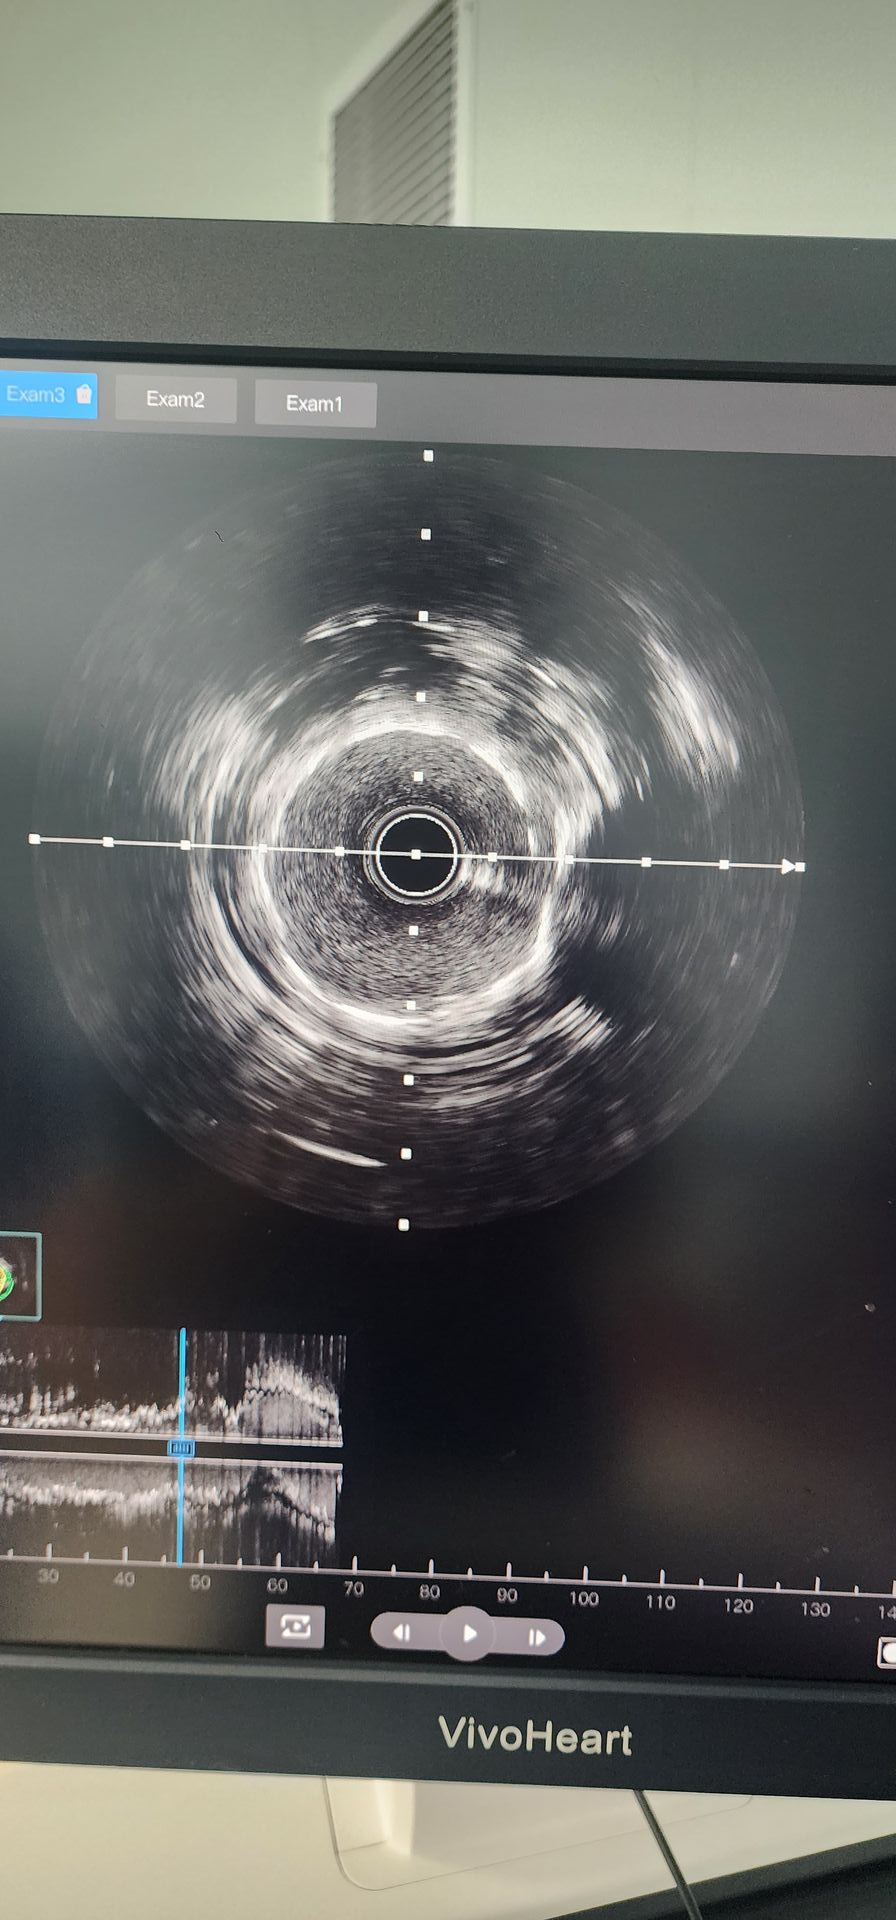

La angiografía coronaria reveló calcificación severa con 95% de estenosis en la arteria circunfleja proximal y 85%-90% de estenosis calcificada en la arteria coronaria media derecha.

Arteria circunfleja proximal: La predilatación inicial con un balón de 2,0 × 20 mostró resultados pobres. A continuación se usó un catéter de dilatación con balón IVL coronario de Lepu de 2,5x12, administrando cuatro ciclos, fracturando con éxito la lesión calcificada. Después de una mejora significativa en la estenosis, se implantó con éxito un stent de 2,5 × 14, con resultados angiográficos satisfactorios.

Arteria coronaria media derecha: La predilatación inicial con un balón de 2,5 × 20 dio como resultado una mejoría limitada. A continuación se usó un catéter de dilatación con balón IVL coronario Lepu de 2,5x12 durante dos ciclos, mejorando significativamente la estenosis en la lesión calcificada. A continuación, se implantó con éxito un stent 3,0 × 19, que produjo resultados angiográficos satisfactorios.